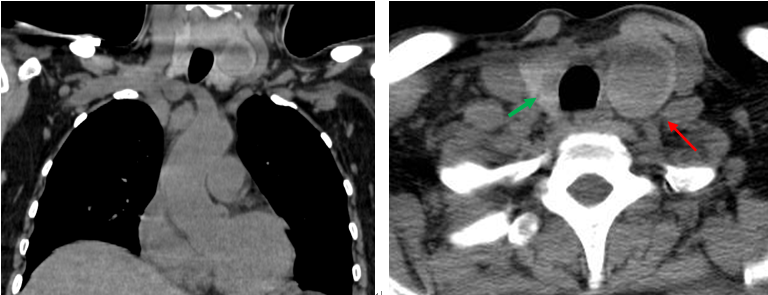

患者同期甲狀腺CT平掃檢查所見(jiàn):

甲狀腺形態(tài)增大,雙葉見(jiàn)類圓形低密度影,大小分別為2.4×2.9cm(左,紅箭),0.7×1.1cm(右,綠箭)。